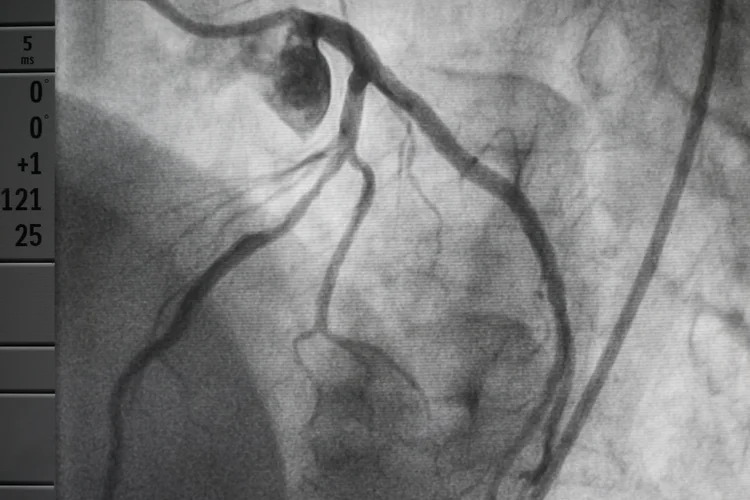

What Is a CT Coronary Angiogram (CTCA) Scan?

A CT Coronary Angiogram (CTCA) scan is a non-invasive imaging test used to check if the

coronary arteries are narrowed, blocked, or have other abnormalities that may

increase the risk of chest pain, coronary artery

disease (CAD), or heart attack.

- You lie flat on a scanner table while the CT scanner captures rapid X-ray images of the heart. The images are then reconstructed into 3D pictures of the coronary arteries and surrounding blood vessels.

A CTCA provides detailed images of the coronary arteries, which are reviewed by a radiologist and may also be assessed by a cardiologist. Your doctor will explain the findings in the context of your overall health and risk profile, and advise on any follow-up tests or treatment if needed.

A CT angiogram is a non-invasive test using CT imaging and contrast dye to create 3D images of the coronary arteries, while a regular angiogram, or catheter angiography, involves inserting a catheter directly into the arteries to inject dye and take X-ray images. CT angiograms are useful for diagnosis and risk assessment, whereas catheter angiography may allow for treatment, such as angioplasty, during the same procedure.

The scan commonly used to detect blocked arteries is a CT Coronary Angiogram (CTCA), which produces detailed images of the coronary arteries to identify narrowing, blockages, or atherosclerosis. Unlike an invasive angiogram, CTCA is non-invasive and uses contrast dye with a CT scanner. In some cases, other imaging tests such as stress echocardiograms or CT calcium scoring may be recommended.